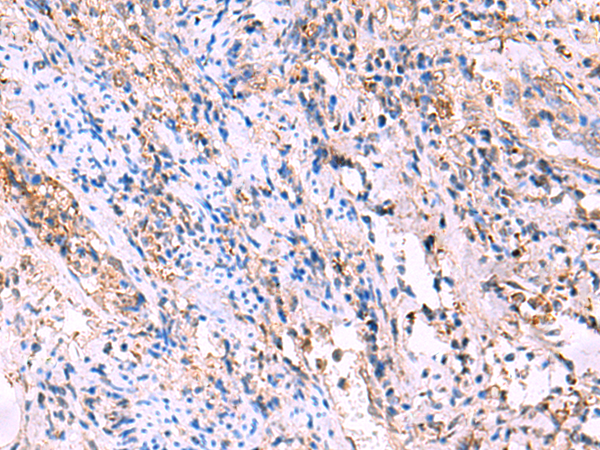

IHC positive control:

Human tonsil and Human cervical cancer

IHC Recommend dilution:

50-300